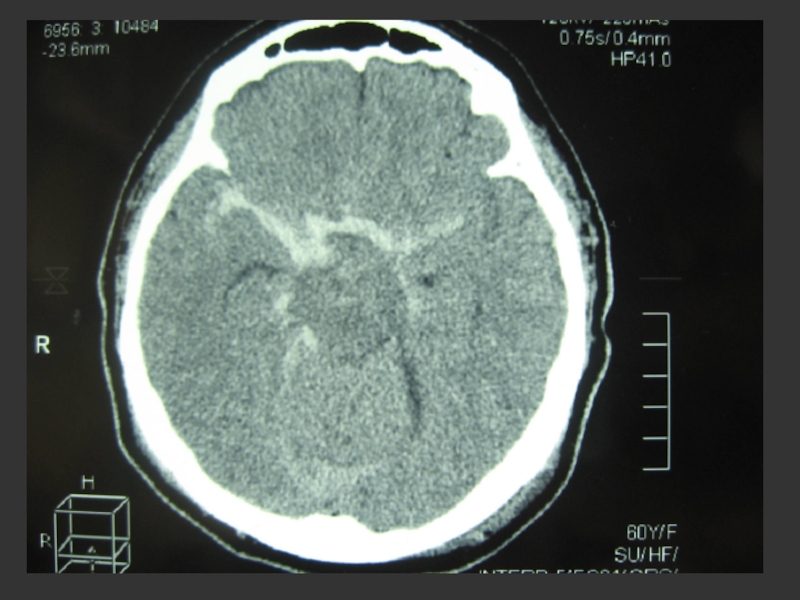

КТ-головы:

КТ-картина массивного субарахноидального кровоизлияния с прорывом крови в желудочковую систему. Киста

прозрачной перегородки. Пристеночное утолщение слизистой оболочки в левой верхнечелюстной пазухи и клетках решетчатого лабиринта с обеих сторон.

Слайд 8По данным КТ субарахноидальное кровоизлияние было классифицировано как 4 степень по

классификации Фишера.